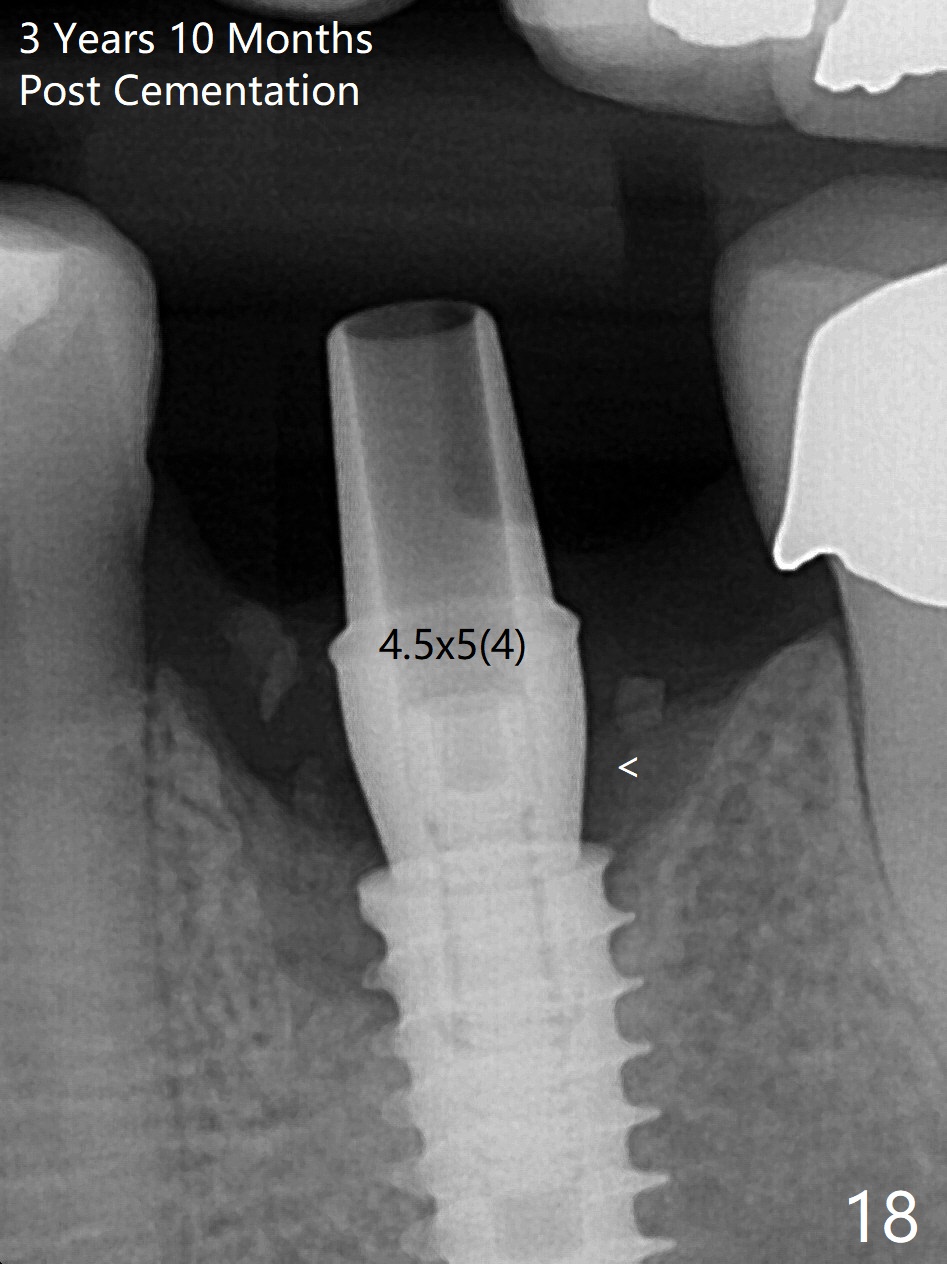

The gingiva looks healthy 8 months postop (3 months post cementation (after abutment screw retightening and addition of porcelain to proximal surfaces, Fig.12). New bone has apparently covered the implant plateau (Fig.13 arrows). Bone density between threads increases 9 months post cementation (Fig.14). There is 2 mm bone superior to the implant plateau mesial and distal 1 year 9 months post cementation (Fig.15,16). The crown/abutment is loose 3 times (3 months (Fig.14), 11 months (between Fig.14 and 15) and 2 years 3 months post cementation). In spite of being stable 3 years 10 months post cementation, a smaller abutment is placed (Fig.17 (PA), 18 (BW)) with impression for a new crown. After intraoral cementation, the new crown/abutment is removed for residual cement removal. When the complex is reseated, it is not smooth, probably due to proximal undercut. Fortunately the abutment appears to be completely seated, followed by 20 Ncm torque (Fig.19).